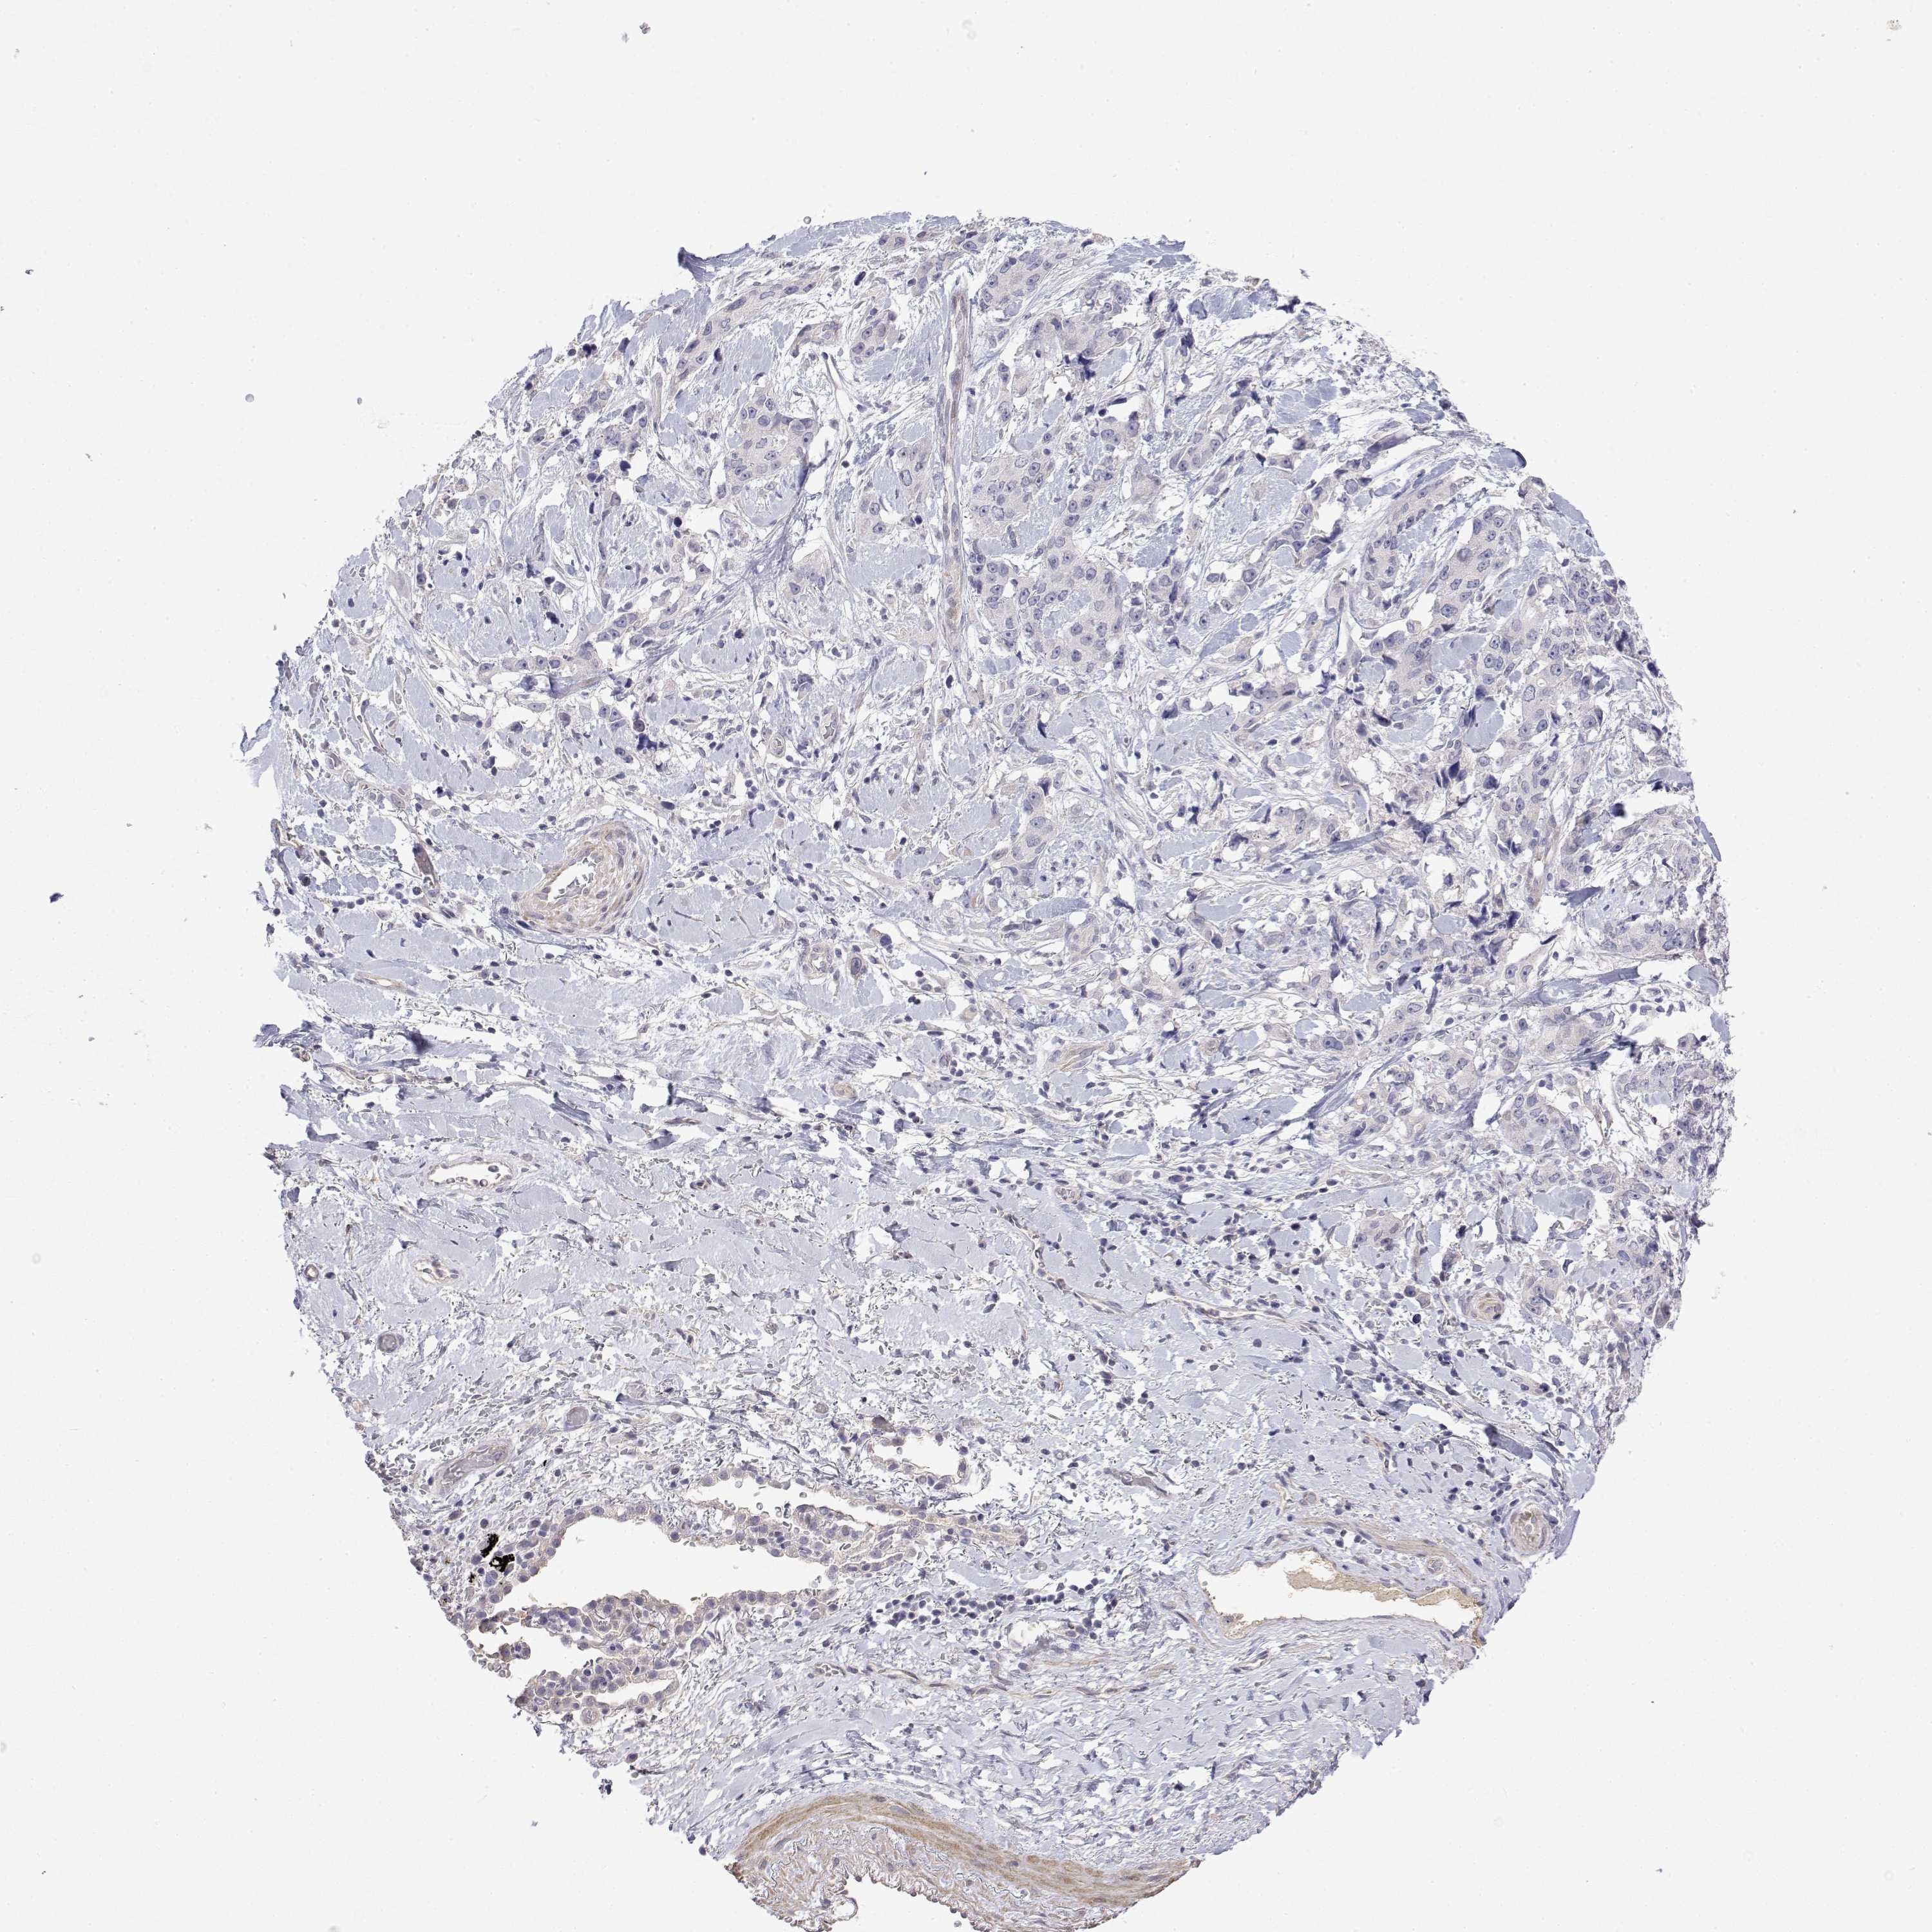

CANCER LUNG CANCER Show tissue menu

Lung cancer

Human cancer